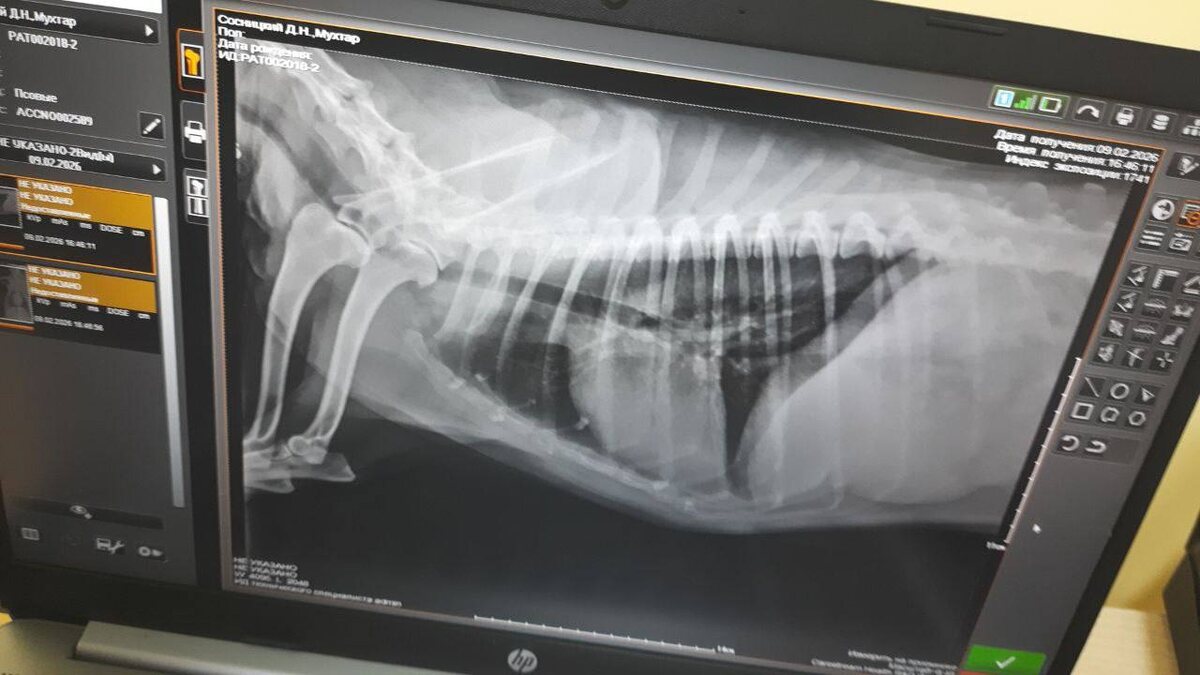

Мухтар вчера ездил снова в клинику. Пневмония разрешилась. На контроль теперь через месяц 🙏

Спасибо большое всем, кто помогал нам и поддерживал с его лечением! Будем надеется , что все теперь будет 👍🤍🤍🤍